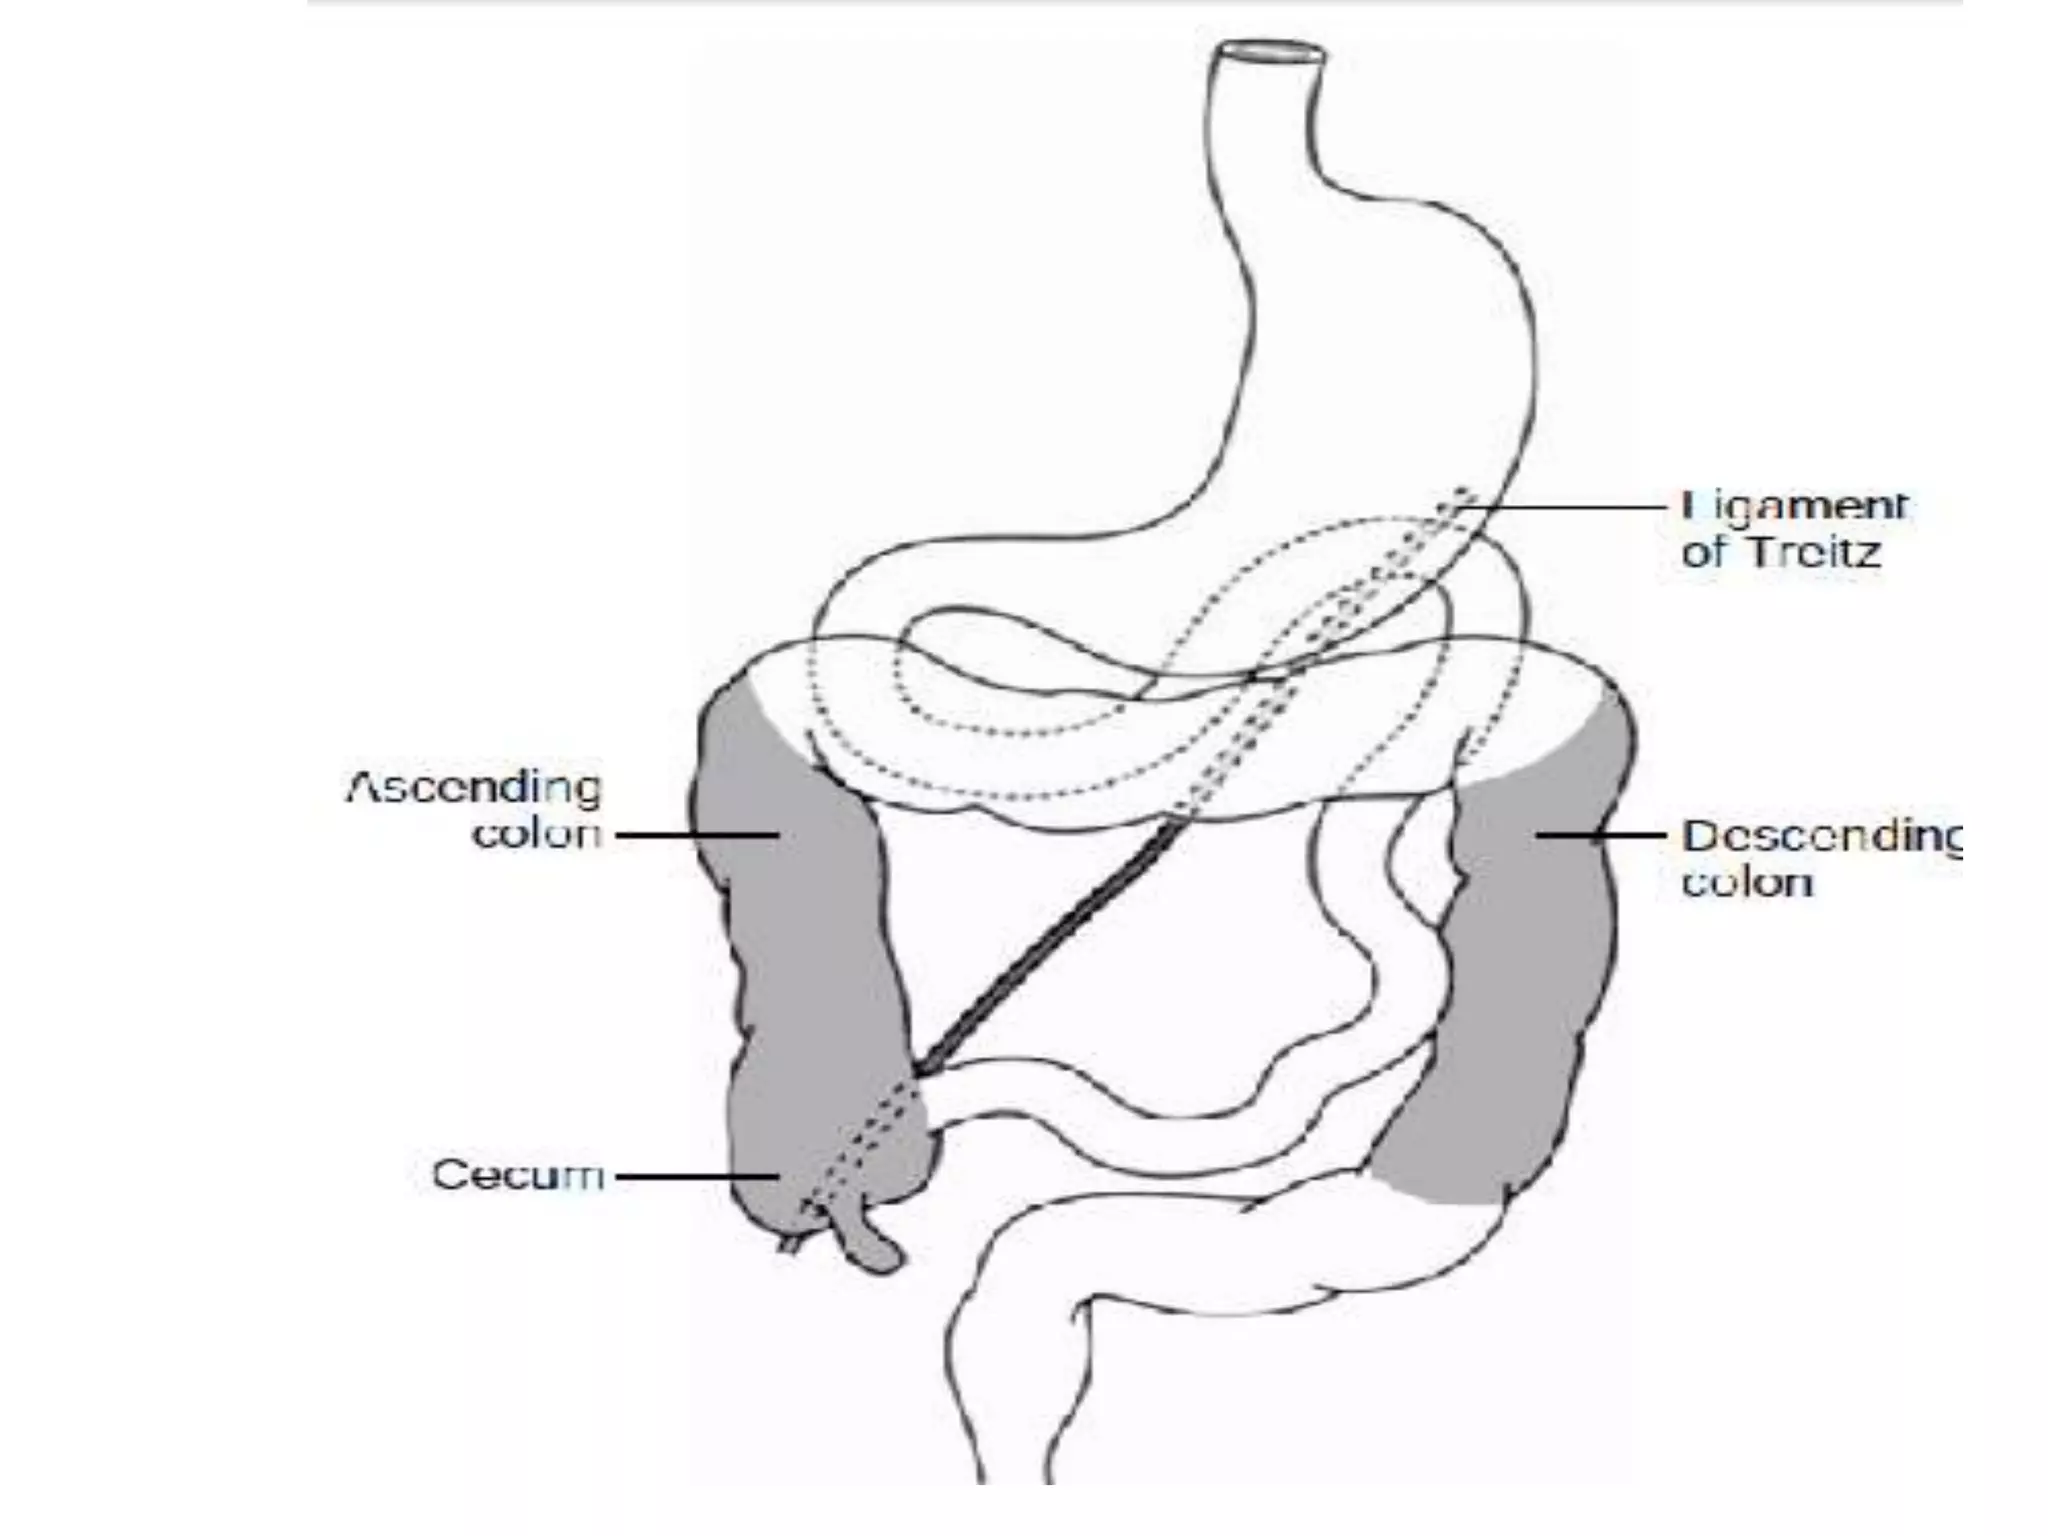

• Through precise embryologic events, the duodenojejunal

junction becomes fixed in the left upper abdomen while

the cecum is anchored in the right lower quadrant.

• The midgut, defined as the portion of the intestine

supplied by the superior mesenteric artery, is thus

suspended from a wide mesenteric base.

Non rotation

Incomplete rotation